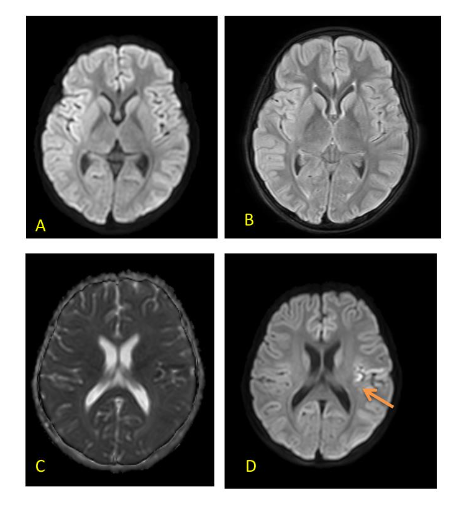

FIRES is usually associated with normal imaging at the outset. Some cases show swelling in the mesial temporal or hippocampal regions presumably from prolonged seizure activity. Late scans show diffuse cortical atrophy due to a combination of brain injury and use of prolonged steroids.

FIG 6 A–D: Fever induced refractory epilepsy syndrome (FIRES) – 8-year-old with onset of refractory seizures on Day 7 of febrile illness. Initial MRI (T2/FLAIR) images are normal (A,B). Subsequent scan done 10 days later showed diffusion restriction in left peri-Rolandic area – arrow (C,D). EEG showed persistent electrical seizures in left > right occipital regions which responded well to Midazolam and Ketamine infusion along with ketogenic diet.